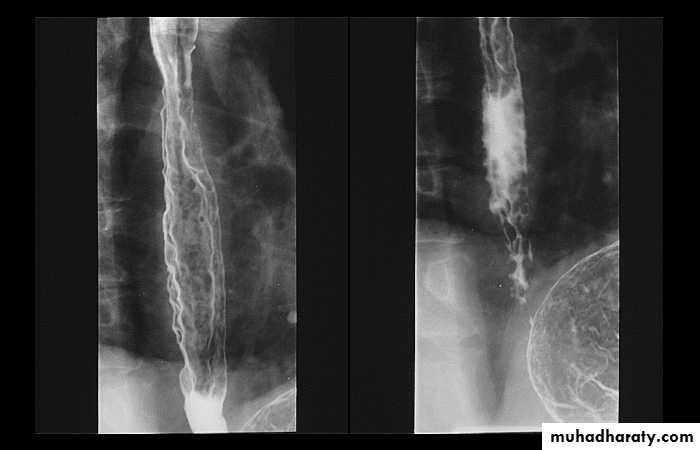

1-Dilatation of venous plexus in the wall of the esophagus due to increased pressure ( portal H.T.).

2-Important cause of Hematemesis .

3-Early changes seen in the mucosa (D.C.) loss of parallelism with thick and tortuous folds.

4-Later multiple small filling defects (fine cobble stone).

5-In advanced stage large filling defects ( coarse cobble stone ) .

6- More advanced stage elongated and worm like filling defect .

7-The changes are seen at lower third and gastric fundus.

Esophageal Varieces